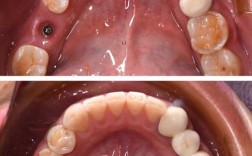

虎牙之所以能成为“种植牙候选对象”,与其自身解剖结构和颌骨条件密切相关,虎牙牙根通常为单根,但长度可达牙冠长度的1.5-2倍,直径较粗壮,这使得其牙槽骨窝较深、骨量相对充足,为种植体提供了良好的初期稳定性,虎牙位于牙弓前部,上方邻近上颌窦(鼻窦底部),下方靠近下颌神经管,但相较于后牙,其与重要解剖结构的距离稍远,手术操作时避让空间更大,降低了神经损伤或上颌窦穿孔的风险,虎牙在咀嚼时主要承受前伸和侧向力,而非垂直向的强大咬合力,种植体设计时若选择合适的直径和表面处理技术,完全可满足其力学需求。

- 牙槽骨条件:种植体需要足够的骨高度、宽度和密度,若虎牙缺失后牙槽骨严重吸收(尤其是唇侧骨板),需先进行骨增量手术(如引导骨再生术、自体骨移植等),待骨量充足后再种植。

虎牙缺失后,唇侧骨板因缺乏生理性刺激会快速吸收,若吸收量超过2mm,直接种植可能导致种植体唇侧暴露,影响美观和长期稳定性,此时需先进行骨增量,常用的方法包括:

- 引导骨再生术(GBR):在骨缺损区植入骨粉(如自体骨、异体骨、人工骨),覆盖可吸收胶原膜,引导骨组织再生;

- 骨劈开术:对于牙槽骨宽度不足但高度足够的情况,将牙槽骨纵向劈开,植入种植体同时挤压骨壁增加宽度;

- 上颌窦提升术:若上颌窦气化明显,骨高度不足,需通过上颌窦内提升(骨量中度不足)或外提升(骨量严重不足)增加骨高度。